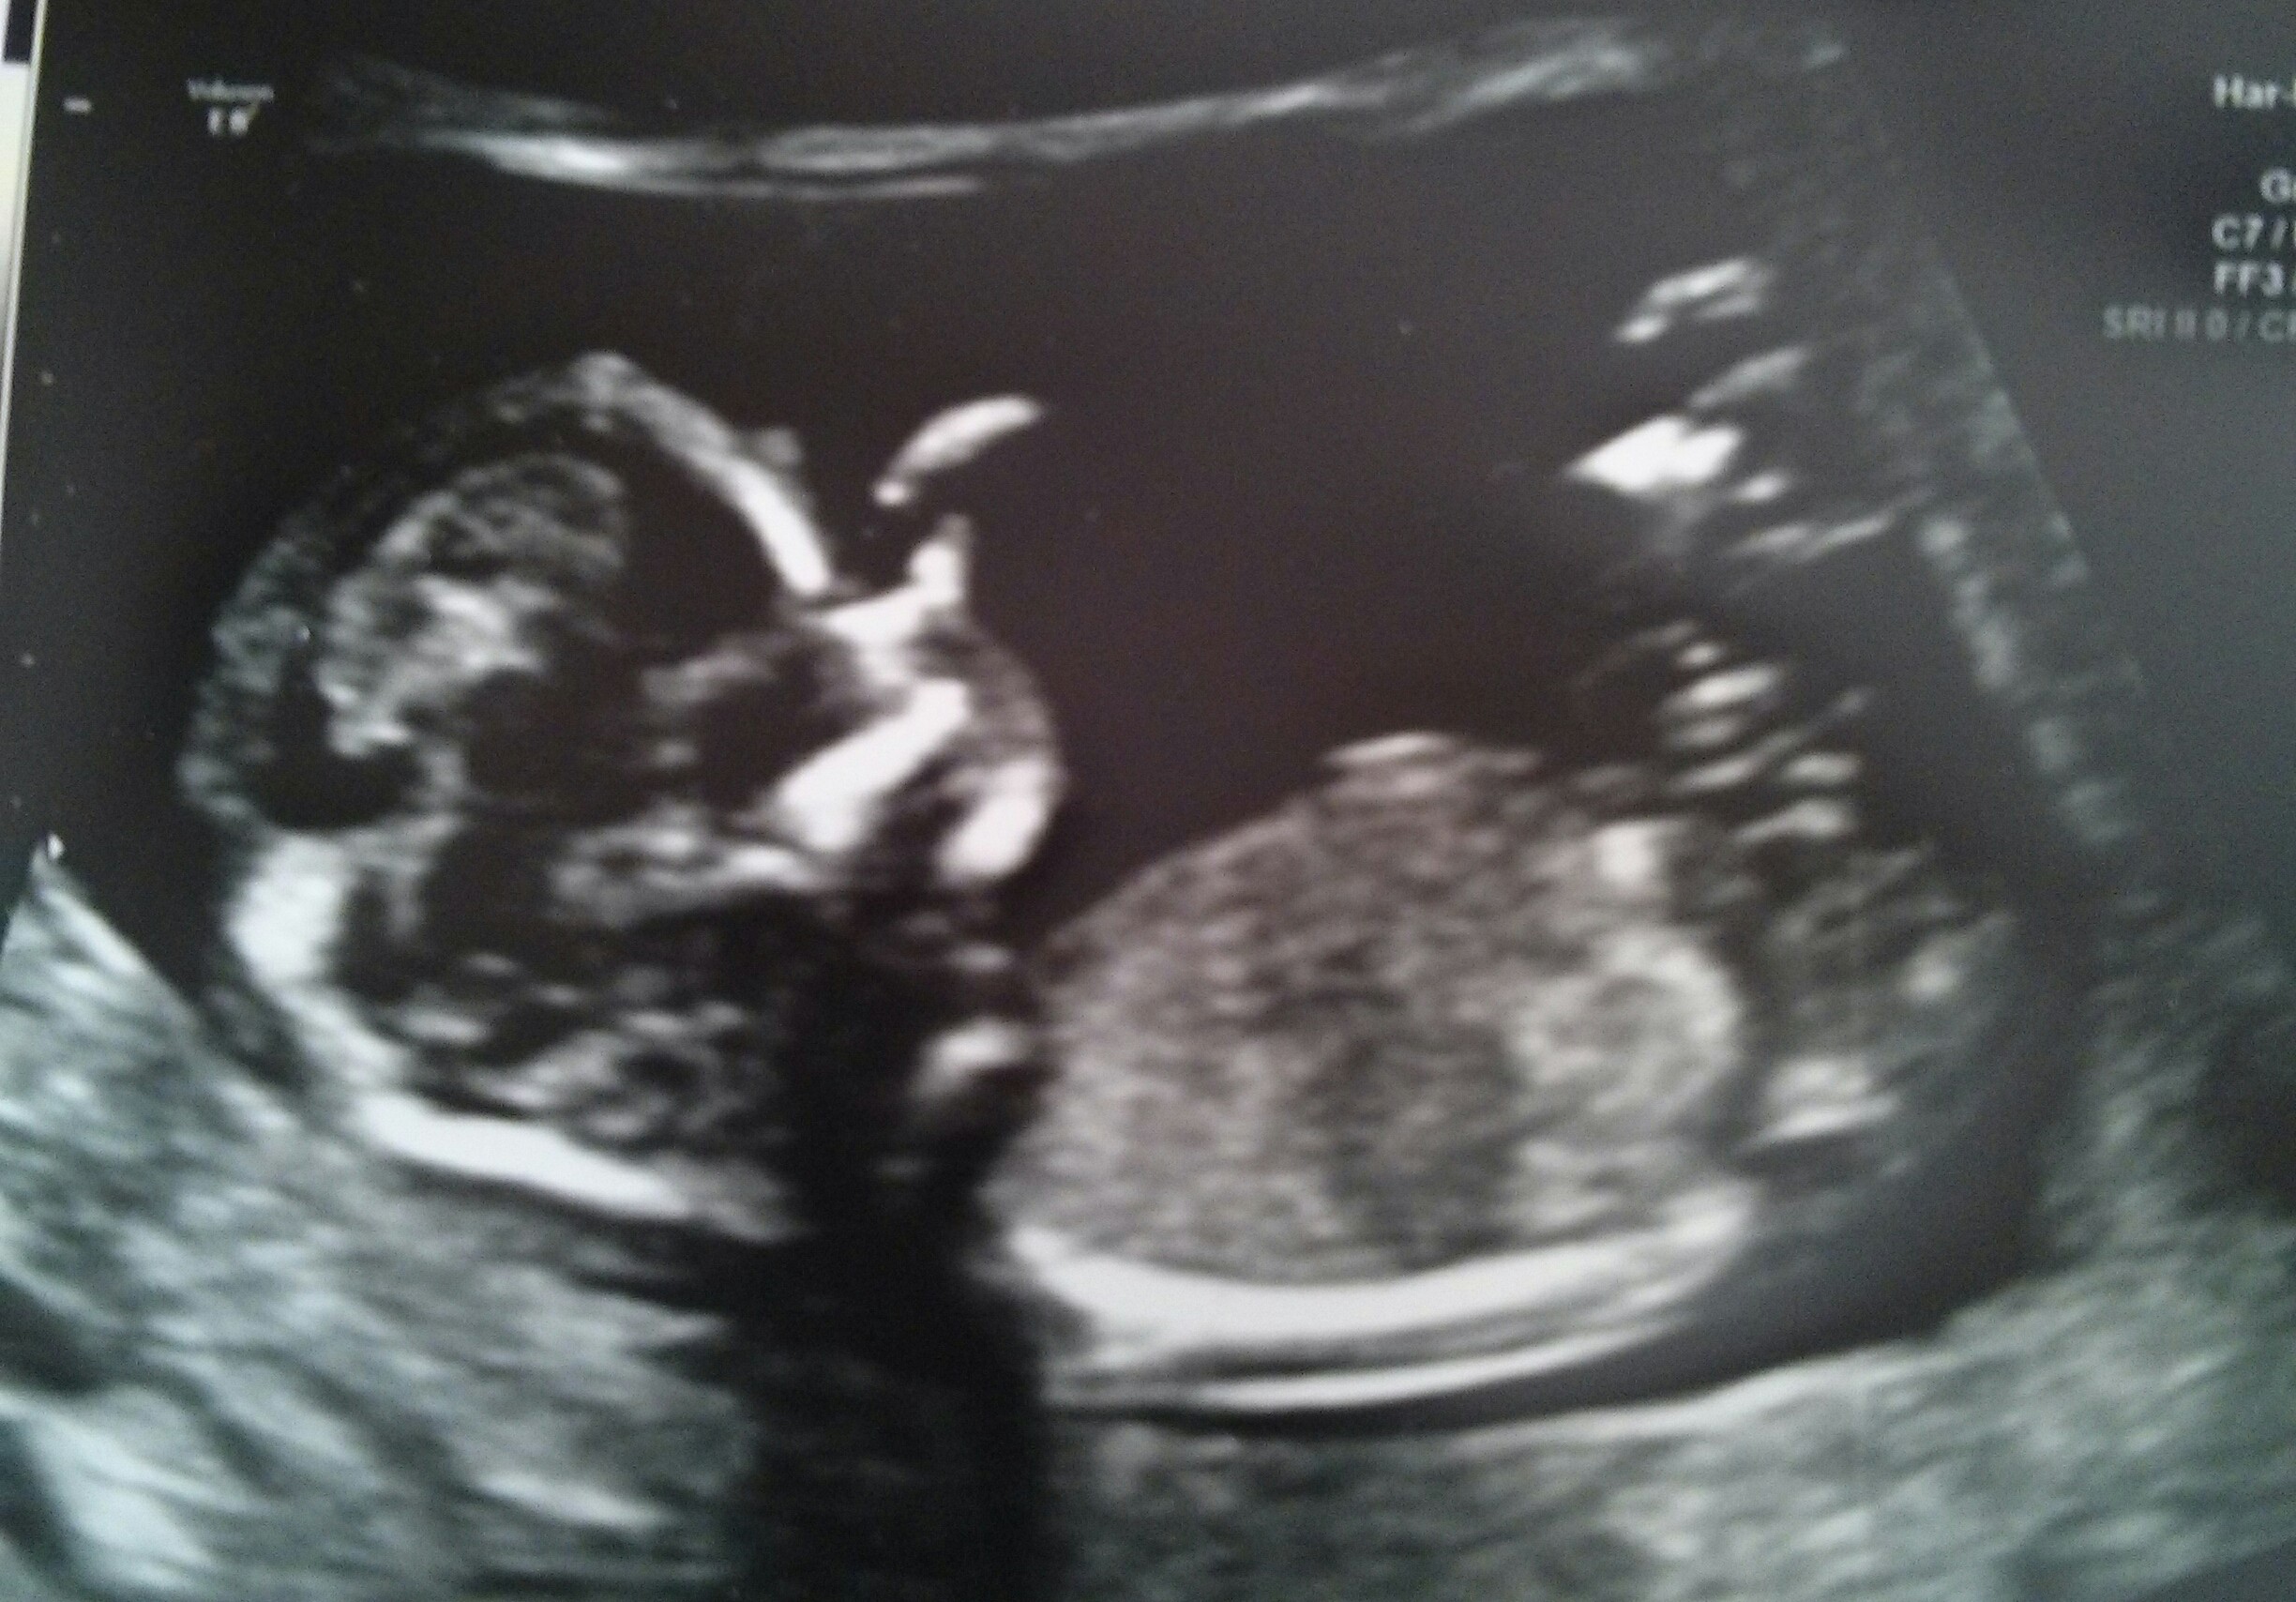

Here's my ultrasound pic for 12W5D. I have no idea if nub is visible or not, but looks girly to me. What do you think? Attachment 18091Attachment 18092

It's too busy in the nub area....I can't clearly see a nub, sorry. :(

I think I see a boy nub in the 2nd pic.

Agree with the other posters plus it's hard to tell if all of the nub has been captured. Tentative blue lean! Congratulations xx